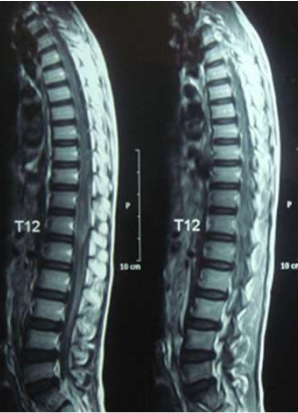

Eight of the ten patients were diagnosed utilizing MRI which showed Dorsal 12 to Lumber 1 or 2 spinal cord swelling with hyper intense patches in T2 images , while the remaining two patient were diagnosed utilizing CT myelogram which showed Dorsal 12 to Lumber 1 or 2 spinal cord swelling.

Image (1 & 2) Sagittal MRI of the spine of case (1) showing cauda eguia expansion and hyperintense patches of in the cauda equine of both T1 and T2 weighted MRI

Image (3) Axial MRI of case (1) T1 weighted MRI showing spinal cord expansion and scattered hyperintense patches.